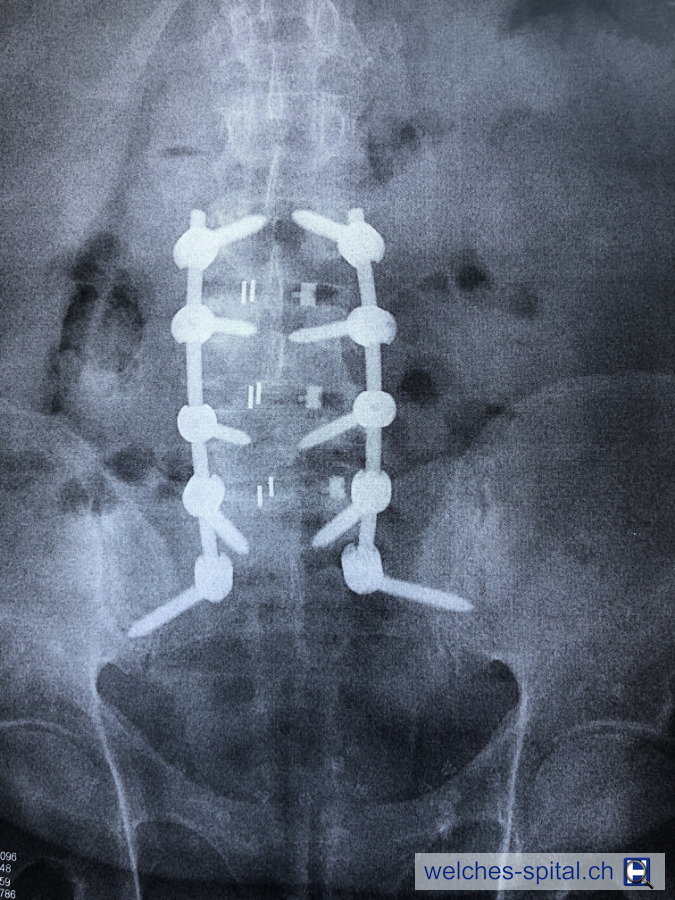

Laminektomie (Wirbelbogenentfernung z.B. bei Bandscheibenvorfall), Infektionsrate

Versteifung der Wirbelsäule von L3 bis S2 mit 10 Schrauben und Knochenentnahme aus dem Beckenknochen. Problemlos abgelaufen. Wunderbare Betreuung von Ärzten und Pflegepersonal. (Chirurg: Dr. Dezsö Jeszenszky)